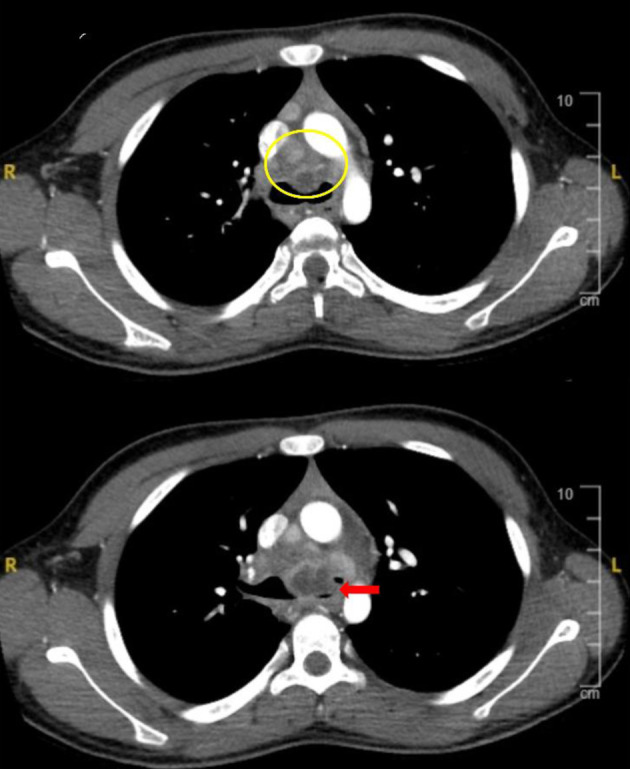

与真菌有关的原发性感染--组织胞浆菌病,在免疫功能正常的宿主中一般没有症状。胸片或计算机断层扫描成像等放射影像学检查可能会偶然发现钙化肉芽肿。不过,即使在免疫功能正常的宿主中,这些原发性感染偶尔也会导致包括呼吸系统损害在内的终末器官受累。对于出现呼吸道受累和纵隔腺病的患者,应将组织胞浆菌病列入鉴别诊断。我们介绍了两名因原发性组织胞浆菌感染导致纵隔和气管淋巴结病而出现肺部受累的儿童患者。第一例患者因胸腔积液导致呼吸困难,第二例患者因气管受压导致呼吸困难。本文介绍了荚膜组织胞浆菌的基本微生物学,介绍了以前有关原发性呼吸道受累的报道,并讨论了诊断和治疗方案。

Primary infection related to the fungus, histoplasmosis, is generally asymptomatic in immunocompetent hosts. Calcified granulomas may be noted incidentally on radiologic imaging such as chest radiographs or computed tomography imaging. However, even in immunocompetent hosts, these primary infections occasionally result in end-organ involvement including respiratory compromise. Histoplasmosis should be included in the differential diagnosis of patients presenting with respiratory involvement and mediastinal adenopathy. We present two pediatric-aged patients who developed pulmonary involvement related to a primary histoplasmosis infection that resulted in mediastinal and tracheal lymphadenopathy. These led to respiratory compromise due to pleural effusion in the first patient and tracheal compression in the second. In this paper, the basic microbiology of Histoplasma capsulatum is presented, previous reports of primary respiratory involvement presented, and diagnostic and therapeutic options discussed.